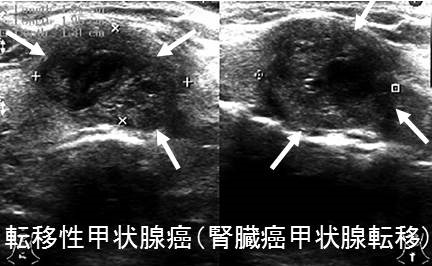

転移性甲状腺癌(他臓器癌から甲状腺へ転移)は①乳癌②肺癌(最多)③腎臓癌(臨床的に最も問題)④悪性黒色腫⑤胃がん・大腸がん・食道がんなど。超音波エコー検査で①低エコー領域②腺腫様甲状腺腫・良性濾胞腺腫・甲状腺濾胞癌と見分け付かず。癌性リンパ管炎をおこすと急激な前頚部腫脹、びまん性甲状腺腫、圧痛、破壊性甲状腺炎(甲状腺中毒症)、エコーで①びまん性低エコー像②樹枝状低エコー(拡張したリンパ管)③甲状腺腫大のみでSOL・低エコーを形成せず亜急性甲状腺炎・急性化膿性甲状腺炎と鑑別要。穿刺細胞診で低分化癌、未分化癌と判定され簡単に診断可能。

- 腎臓癌(臨床的に問題となる転移性甲状腺癌の中で、もっとも多い) (腎臓癌と甲状腺癌)

腎細胞癌甲状腺転移は、原発巣摘出後かなり長期で見つかる事が多く、平均7.7(3.3-13)年とされます(ANZ J Surg. 2021 Apr;91(4):708-715.)。超音波(エコー)検査上、腺腫様甲状腺腫、良性濾胞腺腫(淡明細胞型)、悪性の甲状腺濾胞癌と見分けが付きません。また、腎細胞がん甲状腺転移における穿刺細胞診の診断率は低く11%です。(Ultrasonography 2017; 36(3):252-259.)

転移性甲状腺癌の超音波検査(エコー)所見は、

- 低エコー輝度、あるいは低エコー領域

結節型、びまん型いずれもあり(Surg Today. 2014 Jan;44(1):55-61.)

- 結節型は腺腫様甲状腺腫、良性濾胞腺腫(淡明細胞型)、甲状腺濾胞癌と見分けが付きにくい